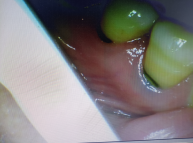

楔状缺损,临床上常见的口腔疾病,常常因为过力的横刷牙齿所导致,有患者来就诊时,常常会说吸口冷风喝点凉水牙齿都有感觉,怀疑是蛀牙,其实还有可能是楔状缺损。

泰安牙科